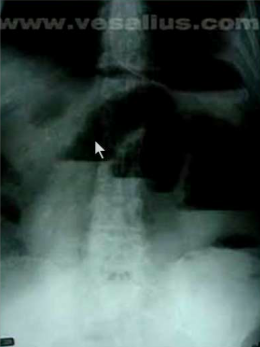

What are you looking for when you take an x-ray of a patient presenting with obstruction?

Air-fluid levels.

Free air. It typically represents a perforated ulcer or ruptured diverticulum.